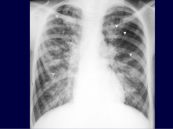

Giãn phế quản là một sự giãn nở vĩnh viễn và dày lên của đường hô hấp đặc trưng bởi ho mãn tính, tạo đờm quá mức, chế độ tồn tại của vi khuẩn, nhiễm trùng cấp tính và tái phát. Bài viết này sẽ nói rõ hơn về hội chứng giãn phế quản trên phim chụp x quang phổi chuẩn. Mời các bạn tham khảo!